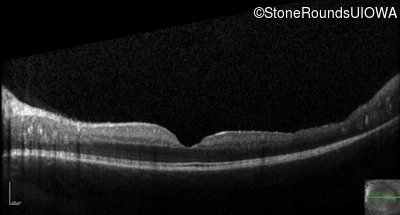

Optical Coherence Tomography - Right - 20/50

Exemplar / OCT Stack